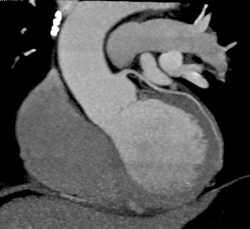

Diagnosis

Multiples Plaques in LAD